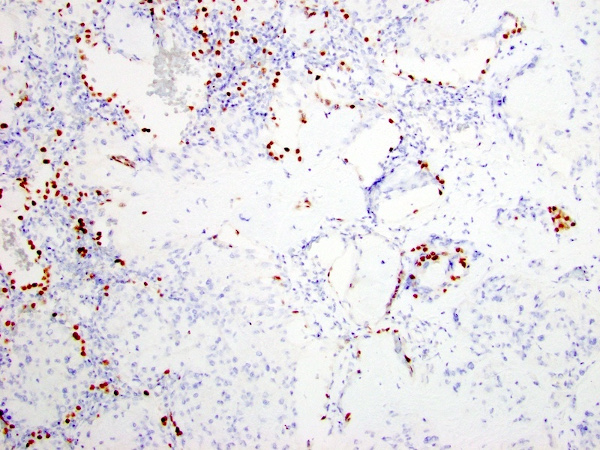

Immunohistochemical stains revealed that the tumor cells were positive for CD31, CD34, and ERG (Figure 3-5). The tumor cells did not mark with pancytokeratin, smooth muscle actin (Figure 6), epithelial membrane antigen, S-100 protein, HMB-45, SOX10, chromogranin, TTF-1 (Figure 7), PAX8, or desmin. No amyloid deposition was identified with Congo red stain.